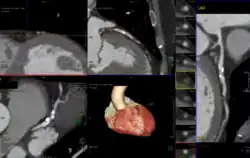

Die aktuellen Qualitätskriterien fordern für die CCTA bei gesetzlich Krankenversicherten einen CT-Scanner mit mindestens 64 gleichzeitig aufgenommenen Schichten. Zunehmend sind Geräte mit 256 Schichten verbreitet, oft mit zwei im rechten Winkel zueinander angeordneten Röntgenröhren. Ein solches Gerät kann das Herz in sechs bis sieben Rotationen aufnehmen, die insgesamt 0,5 Sekunden dauern, d. h. bei ausreichend langsamem Herzschlag im Bruchteil einer einzigen Herzaktion. Es gibt auch spezielle Scanner mit Kegelstrahl und breitem Detektor, die nur eine einzige Rotation ausführen.[11] Um eine geringere Herzfrequenz- und -variabilität zu erreichen, kann vor der Untersuchung ein Betablocker verabreicht werden. Viele Untersucher setzen außerdem Glyceroltrinitrat ein, um den Gefäßdurchmesser der Koronarien zu vergrößern.

Während der Untersuchung wird ein EKG abgeleitet und der Scanner damit gesteuert, sodass die Bildgebung in einer Herzphase mit schwacher Bewegung einsetzt (meist in der mittleren Diastole). Für die Darstellung der Gefäße wird jodhaltiges Kontrastmittel in hoher Konzentration und hohem Fluss appliziert. Für die Auswertung sind spezialisierte Befundungscomputer üblich geworden, die meist in anderen Räumen aufgestellt sind. Stenosen innerhalb der Koronargefäße können erkannt und ausgemessen werden. Dabei kann unterschieden werden, ob es sich um Stenosen durch kalzifizierte Plaques oder durch nichtkalzifizierte Plaques handelt. Für die standardisierte Befundbeurteilung hat sich der CAD-RADS-Score[12] etabliert, der auch Empfehlungen für das weitere Vorgehen umfasst.